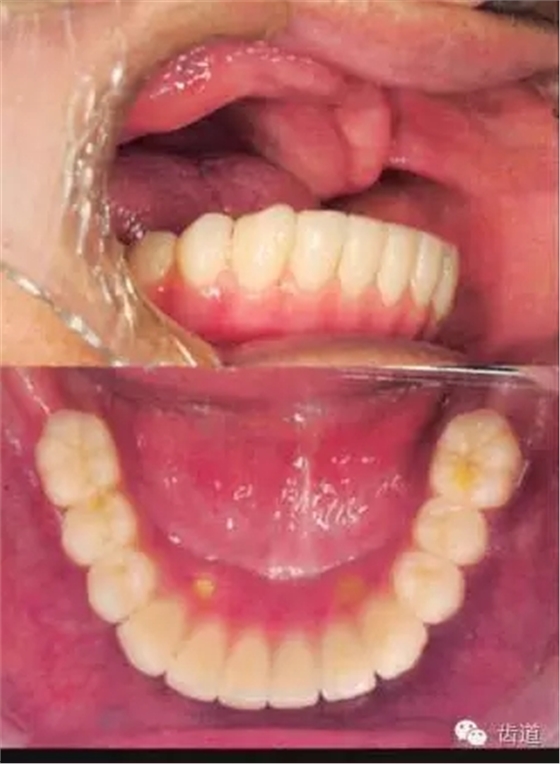

患者男性,81歲,一年前在其他醫(yī)院完成下頜All on Four的種植修復(fù)

因為上頜義齒不適疼痛,要求修復(fù)

患者為重度Class III 類,雙尖牙以前的牙槽嵴嚴(yán)重吸收,前牙區(qū)牙齦松軟

患者不接受反he的面形,要求恢復(fù)正常容貌

患者就診時,義齒組織面有很多的粘著劑